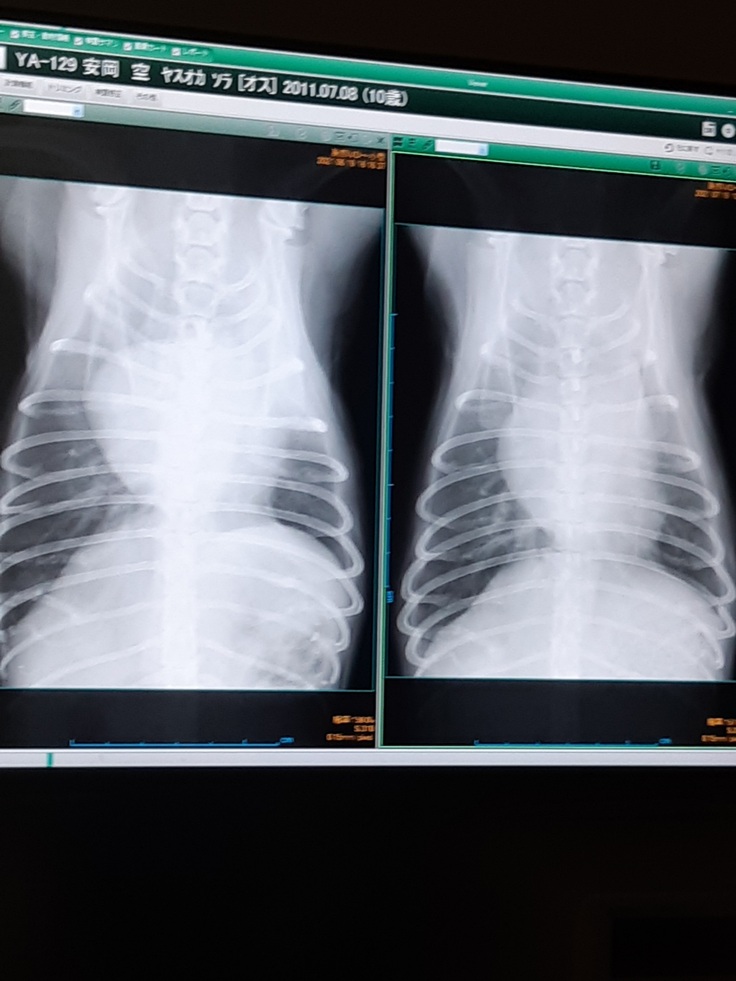

レントゲン検査、心臓も小さくなっています。

術後の後遺症だった問題の肺ですが、画像の左は1カ月前のレントゲン画像で右は今日の画像です、白っぽい影が少し薄くなっていました!よかった!

現在肺は良くなりつつありますが、たまにヒーヒーと呼吸をするので気管支のレントゲンを撮っていただいたら気管虚脱ぎみと言われました。